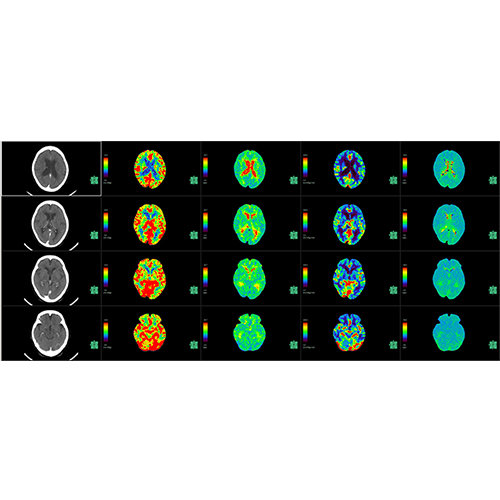

Traditional multi-planar slicing

Designed mainly for CT and MR DICOM modalities.

Multi-planar slicing.

Window/level (brightness and contrast) presets.

Side-by-side comparative assessment for pre- and post-operative scans.